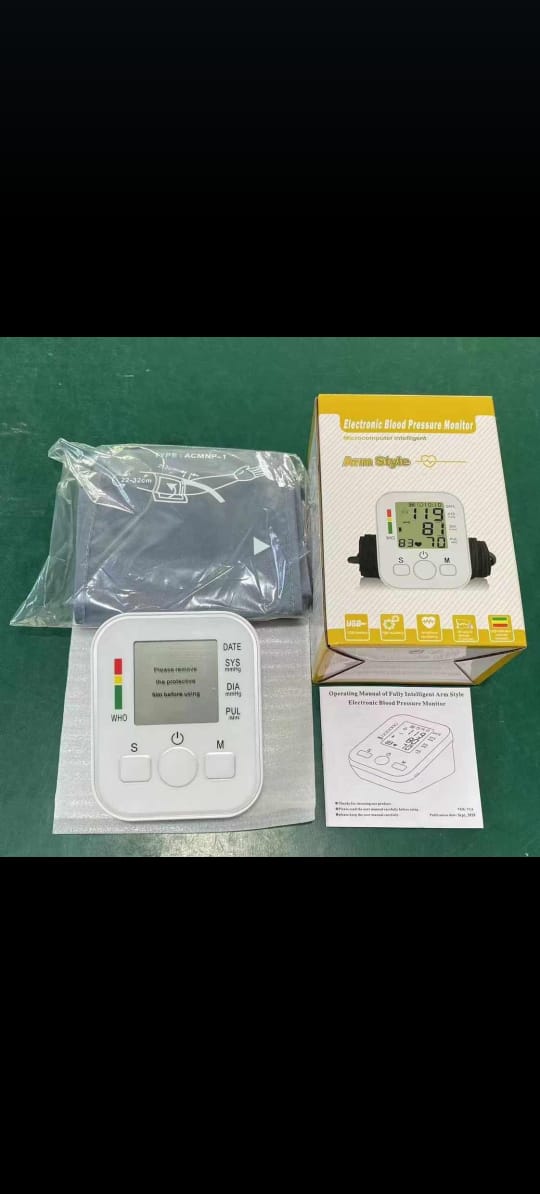

DIGITAL BP - AND MEDICAL

DIGITAL BP - AND MEDICAL

Blood Pressure Monitor

Blood Pressure Monitor

OMRON M1 BASIC

OMRON M1 BASIC

.jpeg) Wave balance BP Moniter

Wave balance BP Moniter

M6 COMFORT AUTOMATIC UPPER ARM BLOOD PRESSURE MONITORE

M6 COMFORT AUTOMATIC UPPER ARM BLOOD PRESSURE MONITORE